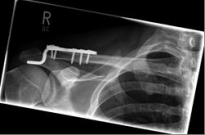

Picture 2: After the operation, the fracture is correctly repositioned and held in position with a titanium plate and two screws..